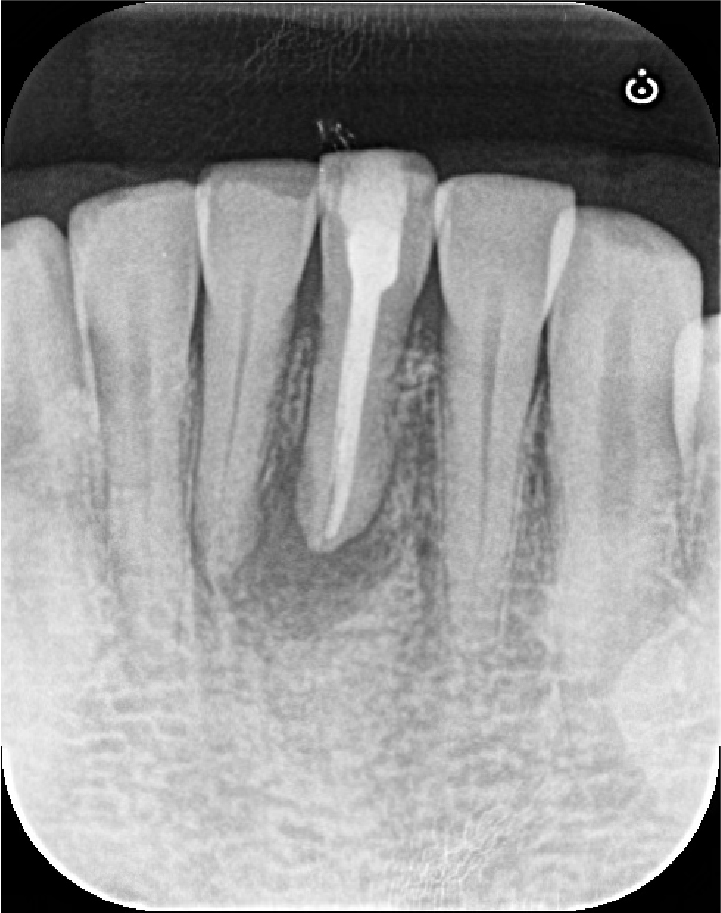

レントゲン写真にて、根の先の黒い影(骨の吸収像)の縮小傾向が認められました。

わずかにまだ黒い影が残っているため、さらに追加で6ヶ月、術後12ヶ月まで経過をみることになりました。

12ヶ月後の経過観察

12ヶ月後のCT画像にて、元々大きく広がっていた骨の吸収が完全に再生していることが確認できました。症状も全くないとのことで、セラミッククラウンを装着して治療は終了となりました。